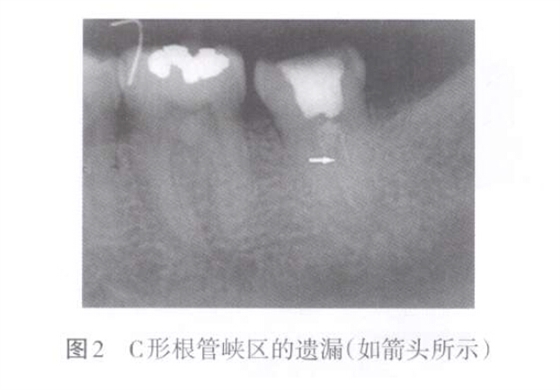

側(cè)副根管主要是指根管側(cè)支、根尖分歧、副根管、管間交通、峽區(qū)等根管變異。側(cè)副根管遺漏表現(xiàn)為上述區(qū)域未能有效預(yù)備和充填(圖2)